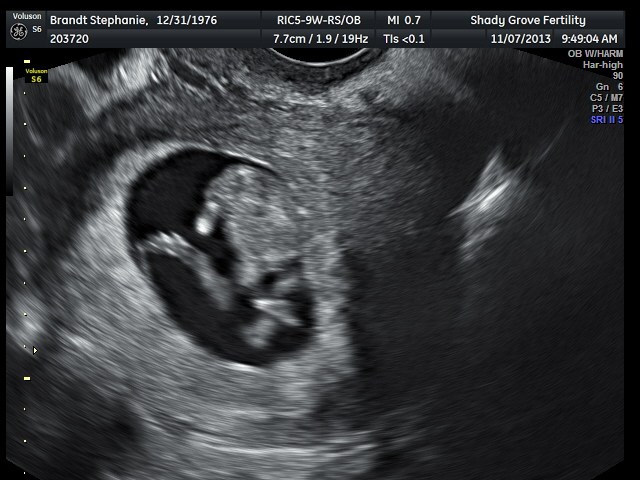

(This is a sonogram pic from out 20 week ultrasound. The tech has NO IDEA why the word “persistence” is on the screen, but I know!)!